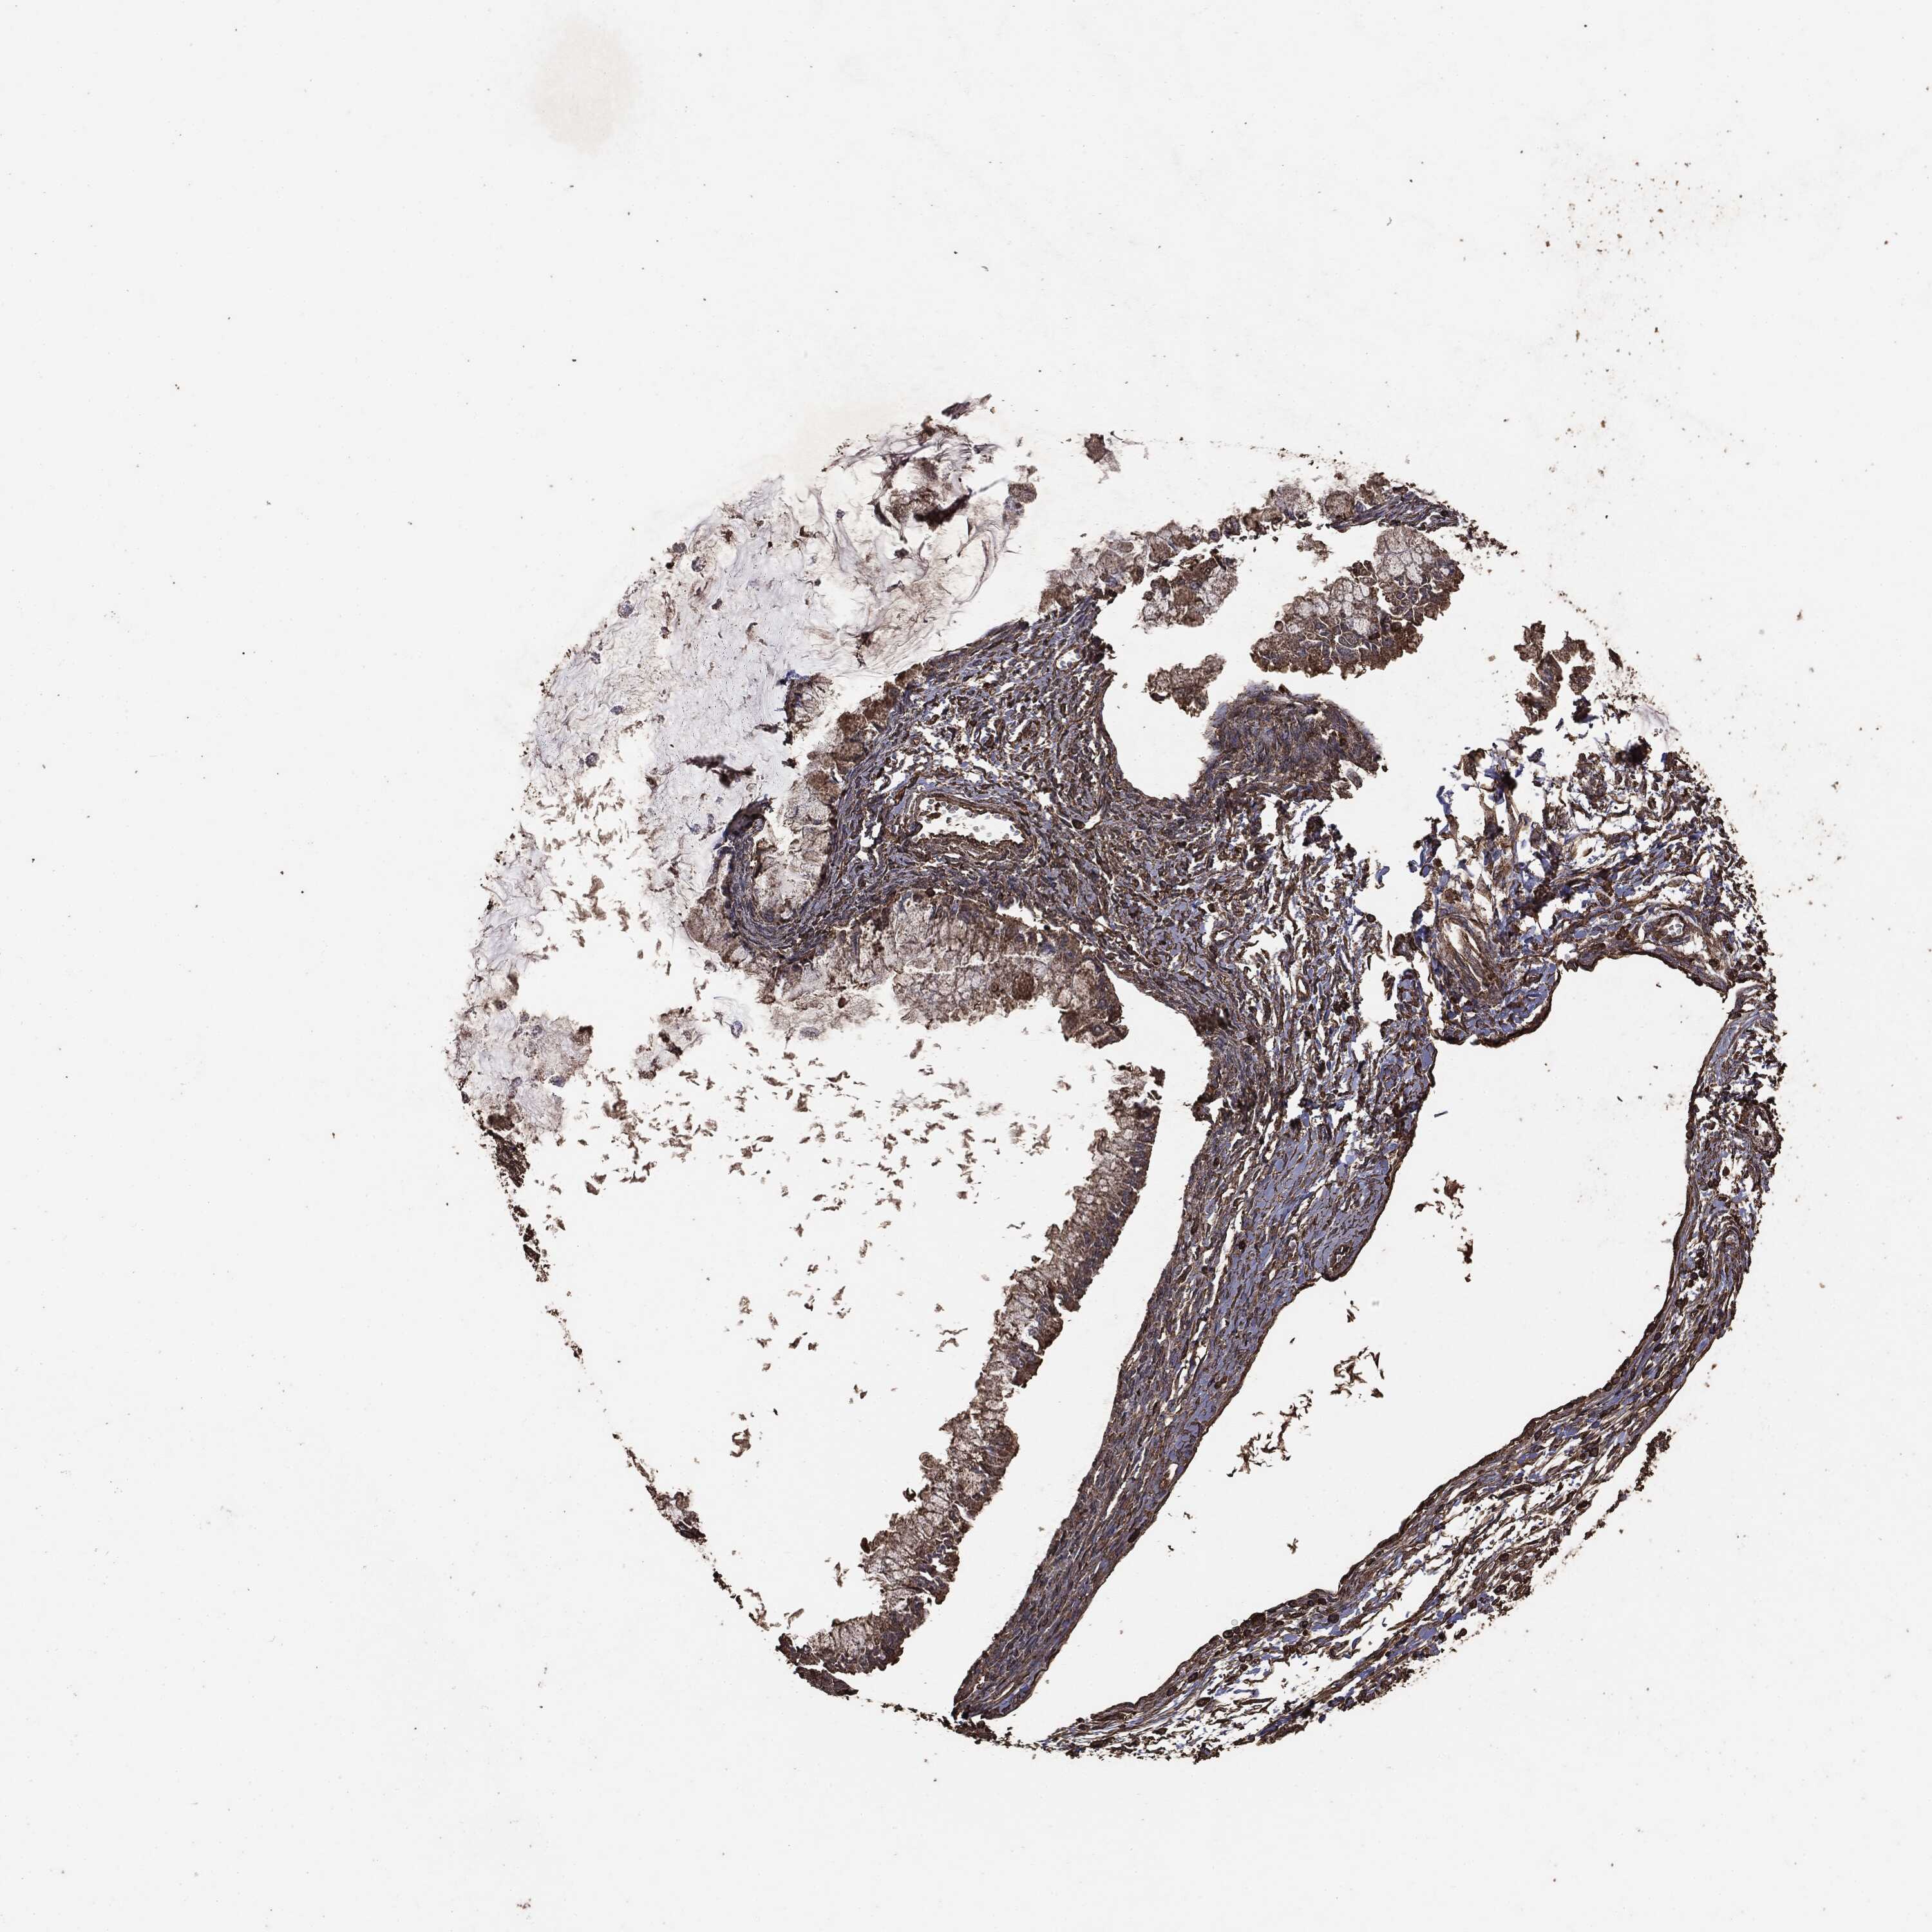

OVARIAN CANCER - Protein expressioni

A mouse-over function shows sample information and annotation data. Click on an image to view it in a full screen mode. Samples can be filtered based on level of antibody staining by selecting one or several of the following categories: high, medium, low and not detected. The assay and annotation is described here.

Note that samples used for immunohistochemistry by the Human Protein Atlas do not correspond to samples in the TCGA dataset.

Antibody stainingi

Antibody staining in the annotated cell types in the current human tissue is reported as not detected, low, medium, or high, based on conventional immunohistochemistry profiling in selected tissues. This score is based on the combination of the staining intensity and fraction of stained cells.

Each image is clickable and will lead to virtual microscopy that enables deeper exploration of all samples and also displays staining intensity scores, fraction scores and subcellular localization as well as patient and tissue information for each sample.

CAB069425